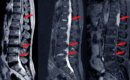

Epidural steroid injections are most effective for individuals who are experiencing chronic back pain caused by the following conditions:

• Herniated or bulging discs

• Spinal stenosis

• Degenerative disc disease

• Sciatica (nerve pain radiating from the lower back down the leg)

• Facet joint arthritis

• Radiculopathy (pinched nerves)

Patients with conditions that involve nerve compression or inflammation of the spinal nerves are often the best candidates for epidural steroid injections. If conservative treatments like physical therapy or oral medications haven’t provided adequate relief, these injections can be a highly effective option to alleviate pain and improve quality of life.